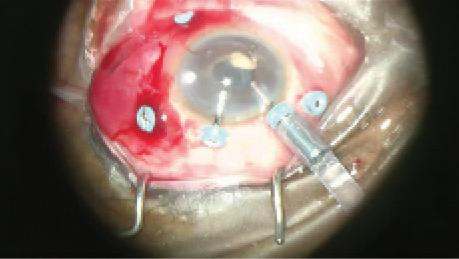

Infectious endophthalmitis is a devastating vision-threatening condition involving inflammation of the entire globe and its intraocular contents (Figure 1). The most common form of infectious endophthalmitis tends to result from direct inoculation of an organism from outside the body (ie, exogenous as opposed to endogenous), most commonly after cataract surgery or intravitreal injection. It tends to present acutely within 3 to 21 days after the procedure.

Figure 1. Postoperative exogenous endophthalmitis presenting as panuveitis. Anterior segment may present with corneal edema, marked anterior chamber cellular reaction, and fibrin inflammatory membrane over the pseudophakic posterior chamber intraocular lens (A). The posterior segment typically has vitritis (seen on echography; B) with retinal hemorrhages.